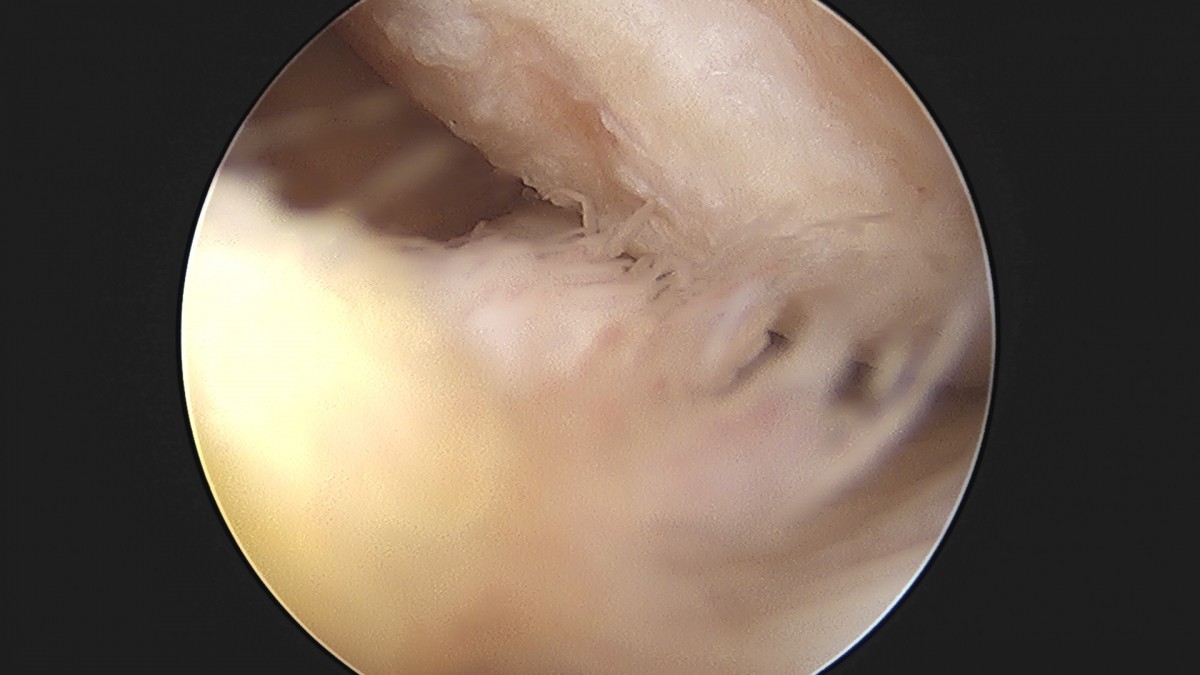

이재상원장님 무릎 반월상 연골판 절제술 김민O 환자

작성자 최고관리자 댓글 0건 조회 365회 작성일 25-09-16 16:10